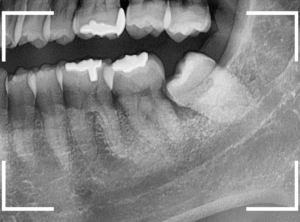

上のケースをより深刻にした状況で、手前の歯とおやしらずの間に食物残渣が日常的に押し込まれているせいで、手前の歯が大きな虫歯になってしまったケースです。

これは早急に治療が必要な状況ですし、抜歯も困難で治療後の痛みや腫れが避けられないです。

さて、このケースの場合は、手前の歯が深い虫歯になっている(赤いライン)上に、おやしらず周囲の歯槽骨(青いライン)も吸収しています。

その骨が吸収した部分に食物残差が押し込まれ、さらに歯槽骨は吸収される悪循環です。

これでは、虫歯で痛くなくても、歯ぐきがとても腫れやすい状況ですし、歯を支える骨が薄くなっているので、少し歯がぐらぐらしてるかもしれません(おやしらずにはさまれているので、現状でははっきりわかりません)。

とにかく、待ったなしの状況であります。